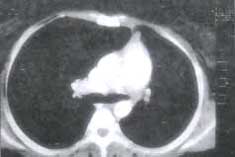

Se realizó TAO simple de tórax (figura N° 5) que confirmó disminución del tamaño del parénquima pulmonar derecho con hemiación del pulmón izquierdo hacia el mediastino anterior, sin otras alteraciones.

En el aortograma torácico se observó el origen de una arteria pulmonar izquierda pequeña en la porción descendente, con un curso similar al de la arteria pulmonar normal (figura No 10). Se realizó TAC de tórax con contraste (figura N° 11) que confirmó la disminución comparativa del tamaño pulmonar izquierdo con hiperinflación del pulmón derecho que tras pasaba la línea media en la porción anterior. No se encontraron anormalidades parenquimatosas o pleurales.

Figura No 11.TAC de tórax.